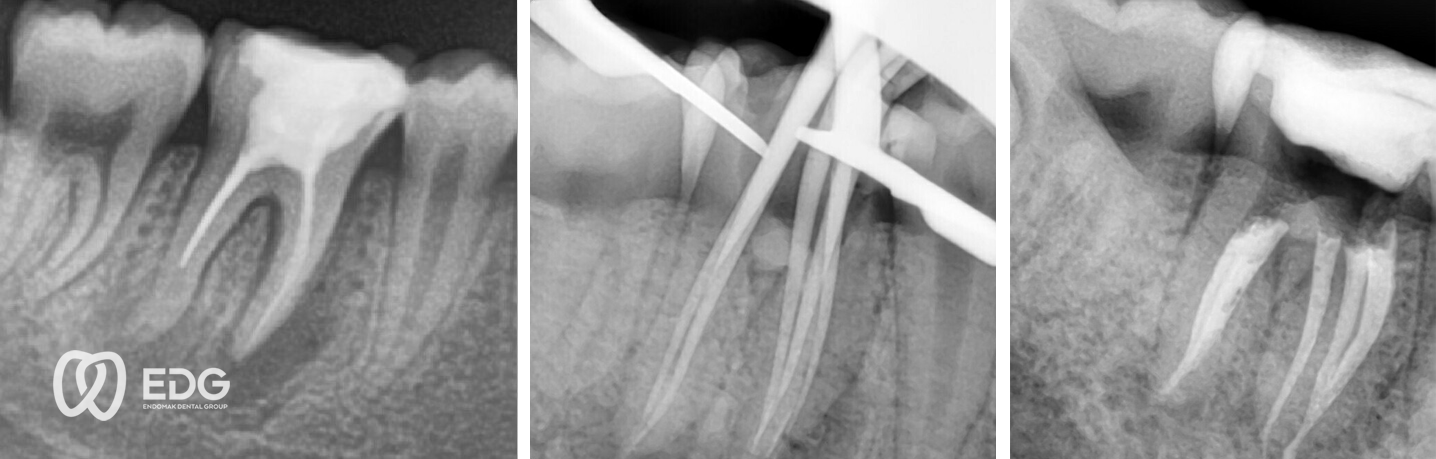

Αυτό επιτυγχάνεται με τη δημιουργία μιας μικρής οπής του δοντιού προς τον χώρο του πολφού, εντοπίζοντας και μετρώντας τους ριζικούς σωλήνες, κατόπιν με τον καθαρισμό τους με απολυμαντικό και διευρυνσή τους με ειδικά όργανα.

Με το μικροσκόπιο, ένα υπερσύγχρονο εργαλείο για ενδοδοντική θεραπεία με πανίσχυρη μεγέθυνση, η απεικόνιση της εσωτερικής κατασκευής της οδοντικής κοιλότητας και των ριζικών καναλιών είναι πάρα πολύ βελτιωμένη. Η απεικόνιση αυτή είναι πολύ σημαντική για την ενδοδοντική θεραπεία επειδή η ακριβής ανίχνευση των ριζικών καναλιών η επιτυχής θεραπεία τους οδηγούν στη μακροχρόνια πρόβλεψη για τη διατήρηση του δοντιού.

Microscopic Endodontic Treatment (MET) step by step procedure. Enjoy it!Made by Dr. Gjorge Gudev

Microscopic Endodontic Treatment (MET) – retreatment of previously treated toothMade by Dr. Gjorge GudevEnjoy it !